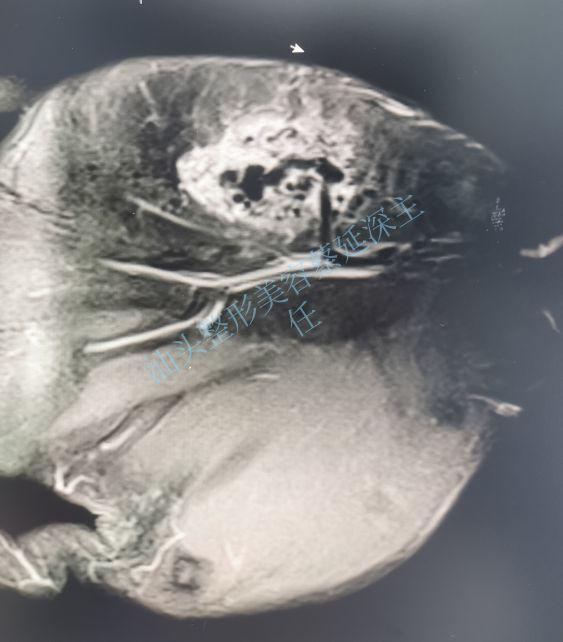

我一摸他小鱼际的地方,还真有一团柔软的东西在一下一下的跳动。凭经验估计还是蔓状血管瘤,也就是一种动静脉畸形。初步考虑要手术切除。为了明确肿物的边界和与周围血管神经的关系。我让他做了核磁共振。

图二是该患者做了核磁共振的结果。左手有一团淤曲变形的血管周围伴有病灶。